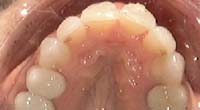

Treatment Time: 7 months

Aligners: 16 Upper